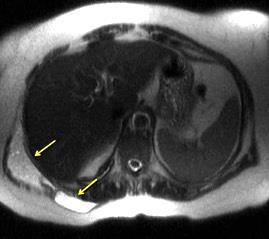

Tumor desmoide (“Fibromatosis agresiva”)

T1: Isointensos con músculos.

T2: Señal intermedia y de alta intensidad.

Presencia frecuente de áreas curvilíneas y lineales dentro de la lesión

Mansour J et al. Diagnostic and Imaging Approaches to Chest Wall Lesions. Radiographics 2022